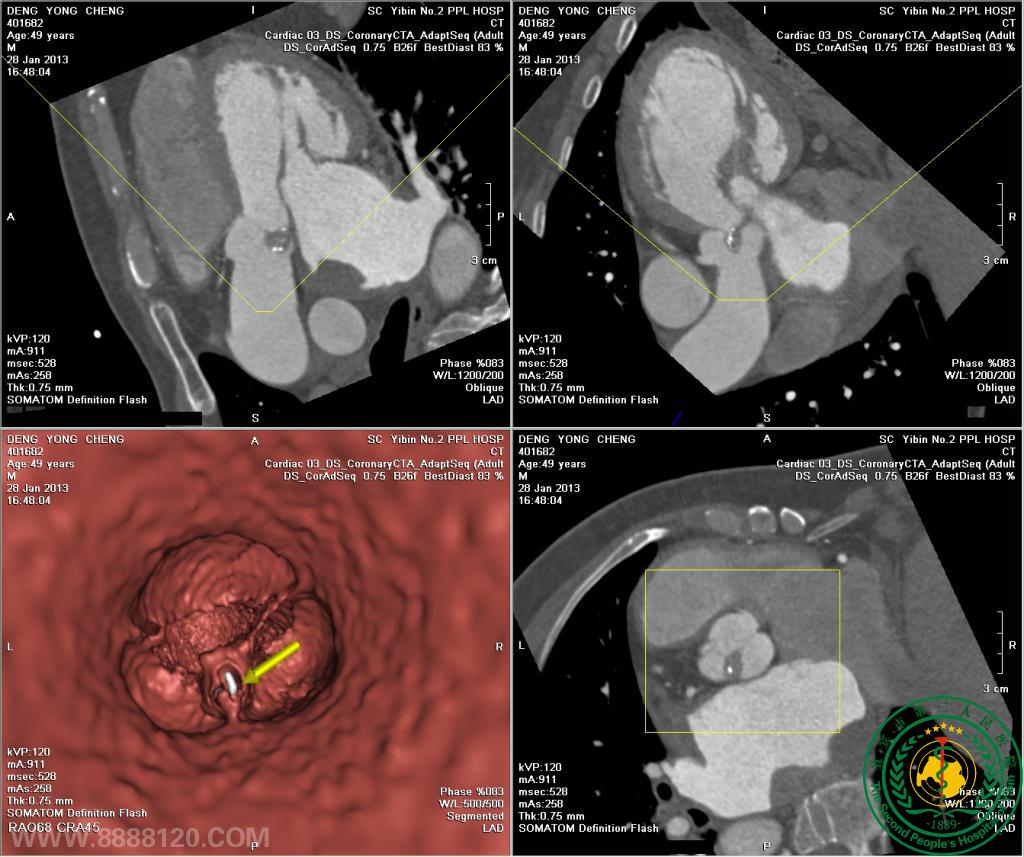

我院开展炫速双源CT对风心病的换瓣或成形术术前、术后评估技术

我院开展炫速双源CT对风心病的换瓣或成形术术前、术后评估技术3829

宜宾市第二人民医院 图文